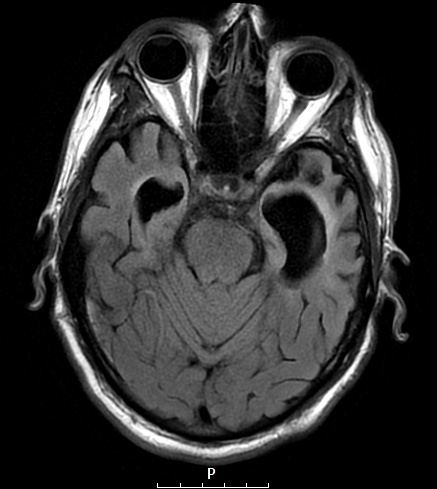

This axial FLAIR image demonstrates marked ventricular dilatation and substantial frontal, temporal (and parietal) lobe atrophy